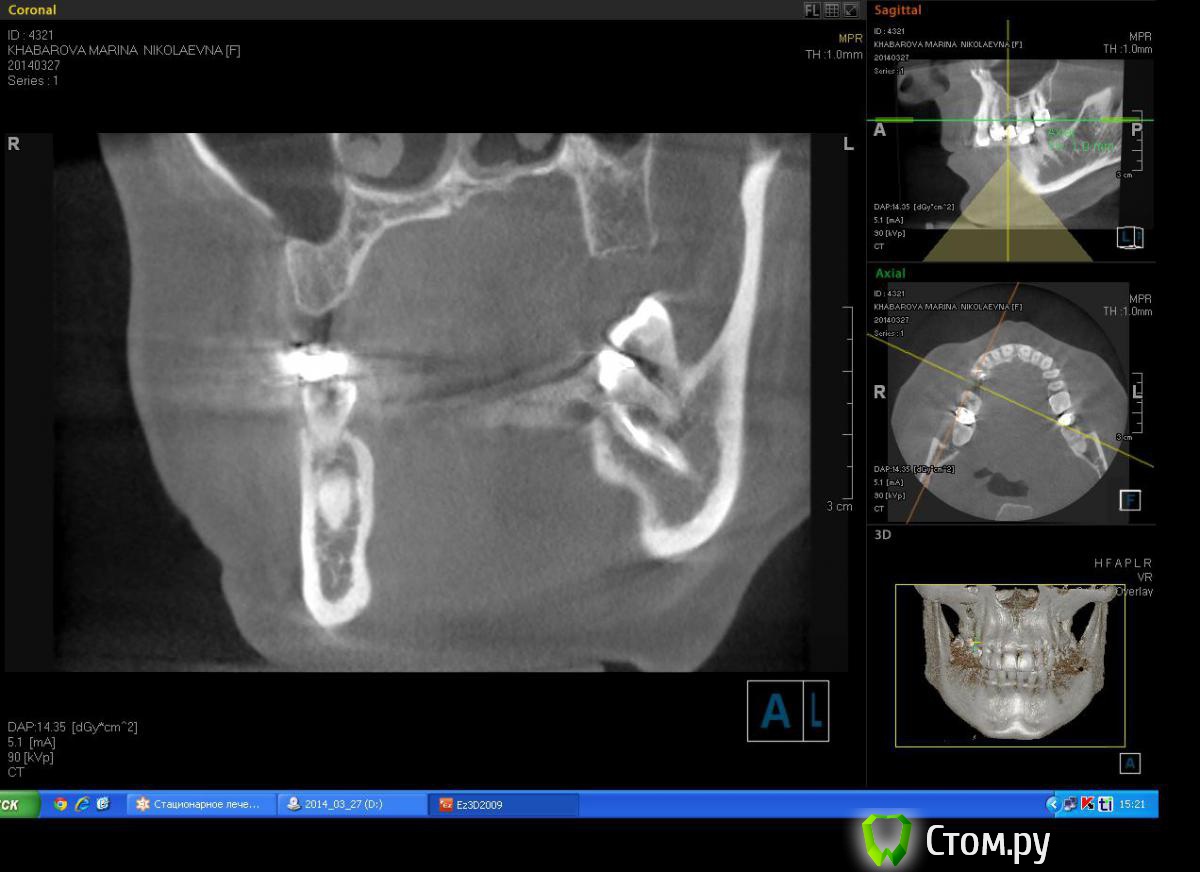

Milanomoda Опубликовано 22 апреля, 2014 Автор Поделиться Опубликовано 22 апреля, 2014 Имплантацию в районе 14 зуба планирую ставить в область язычного корня, только вот вопросик такой, при одномоментном протоколе на сколько примерно заглублять нужно будет имплант? Ссылка на комментарий

DShu Опубликовано 22 апреля, 2014 Поделиться Опубликовано 22 апреля, 2014 4,2 думаю им там тесновато будет. 4,5 тем более.На 14 я бы поставил 3,75*16 (или на 13) на 15 - 3,75*10 бикортикально. Сразу формики, вокруг - графт или без него, кто как любит) 3 Ссылка на комментарий

Milanomoda Опубликовано 22 апреля, 2014 Автор Поделиться Опубликовано 22 апреля, 2014 4,2 думаю им там тесновато будет. 4,5 тем более.На 14 я бы поставил 3,75*16 (или на 13) на 15 - 3,75*10 бикортикально. Сразу формики, вокруг - графт или без него, кто как любит)Если в области 15 делать бикартикальную фиксацию то без синуса(закрытого) не обойтись, а если делать без синуса - то при нагрузке мне кажется слизистая гайморовой среагирует, не даром же от анатомических образований рекомендуют около 2 мм отступать... Ссылка на комментарий